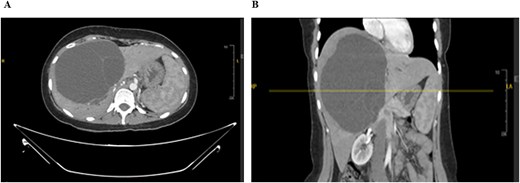

The mass had fine, minimally enhancing septations without any solid enhancing component. Communication with the right intrahepatic biliary ducts was observed, leading to moderate intrahepatic biliary duct dilatation. Magnetic resonance imaging (MRI) of the liver using contrast reveals a large hepatic cystic mass, corresponding to dimensions noted on CT, showing bright T2 signal intensity with thin septations without a solid component, illustrated in Fig. 2.

MRI of the liver: Demonstrating the mass in T2. Mild splenomegaly was noted without focal lesions. A) Transverse view, B) longitudinal view.

Mild splenomegaly (13.4 cm) with no focal lesions was noted, which exerted a mass effect on the patent hepatic vasculature. No osseous lesions or lymphadenopathies were identified. Three smaller bright T2 signal intensity lesions that did not enhance on post-contrast scanning were seen in segments 7 and 6, with measurements 0.2 × 0.1 cm, 0.7 × 0.7 cm, and 0.9 × 0.4 cm, respectively. The consistency of the cyst is evident from Fig. 3.